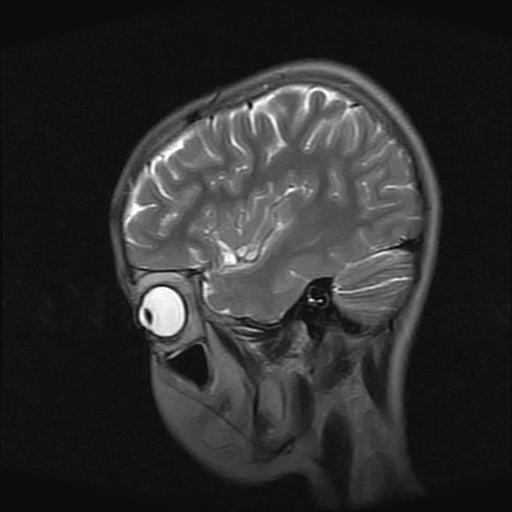

9岁女孩,三岁时诊断为癫痫,一直服丙戊酸钠,现患者一般情况良好,家长复查核磁片,看能否停药..

巨脑回